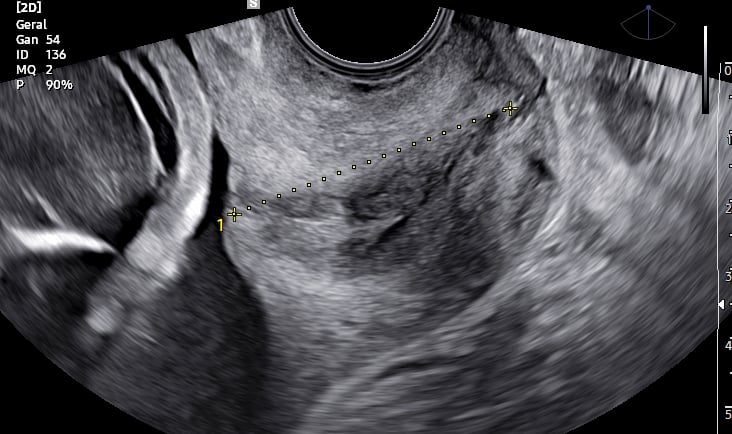

Durante o ultrassom, avaliamos o comprimento do colo do útero por via transvaginal. Um colo curto — geralmente considerado menor que 25 mm — pode indicar maior risco de parto prematuro. Essa medição é simples, rápida e indolor, e pode fazer toda a diferença no acompanhamento da gestação.